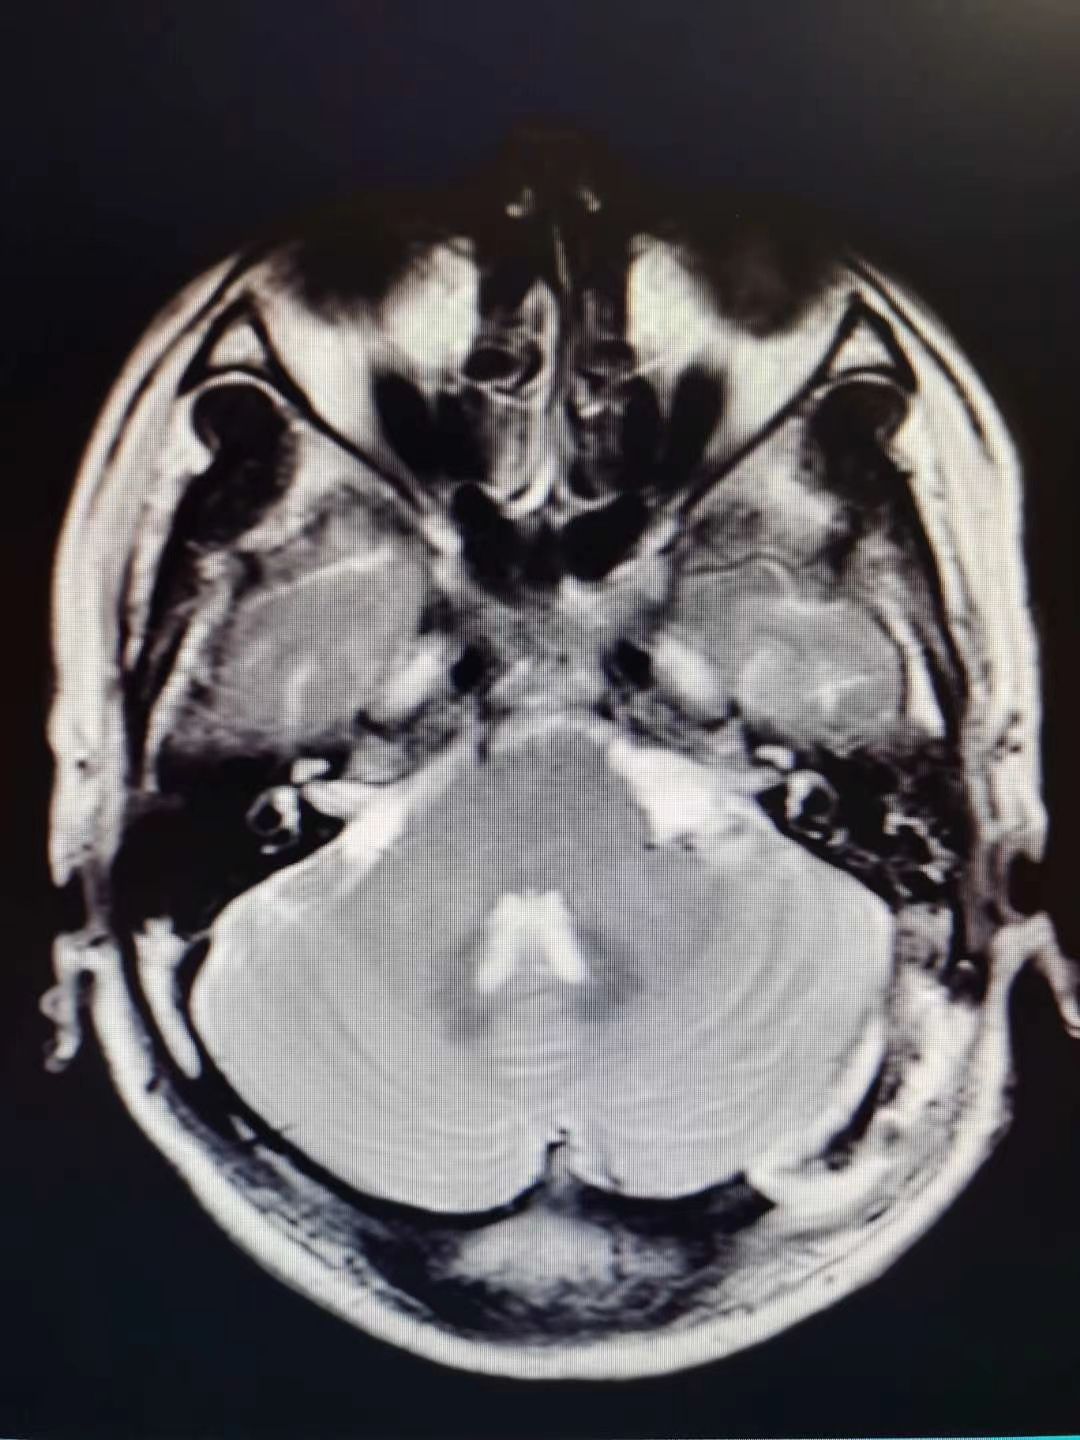

听神经瘤1例

肿瘤全切,术后面神经功能保留完好